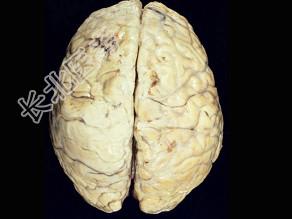

- 单项选择题观察图片所示病理,流脑脑膜炎期的病变特点以下说法正确的为 ( )

A、颅底部炎症粘连可导致脑神经损害

B、早期能发生脑室孔阻塞

C、硬脑膜水肿

D、脑实质无炎症

E、病变主要部位在软脑膜及蛛网膜